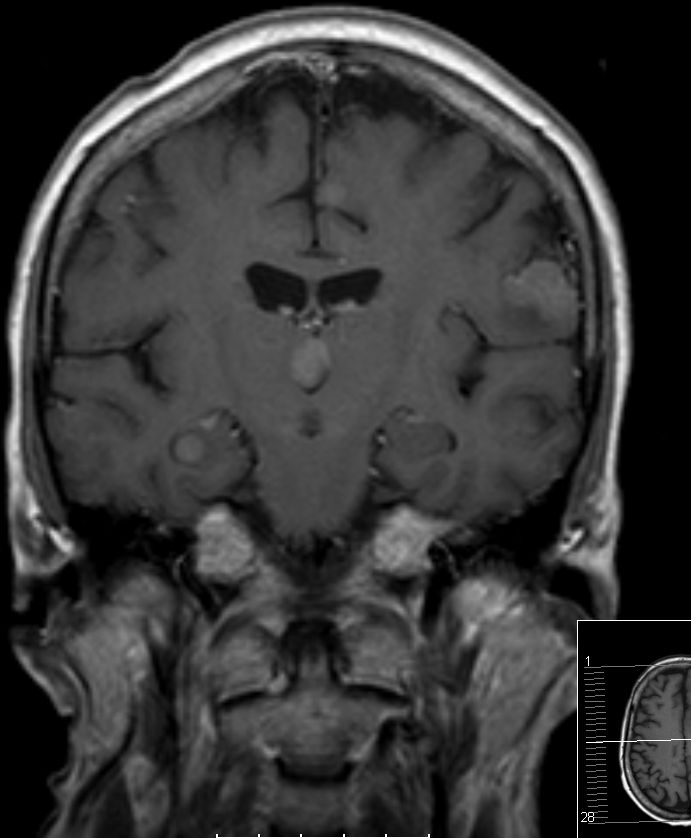

Hirnmetastase

Hirnmetastase links occipital mit ausgeprägtem Ödem.

Im MRT Metastase im rechten Amygdala. Zusätzlich weitere Metastasen.

Patientin mit einer Abducens-Parese. Im MRT Metastase der Medulla oblongata.